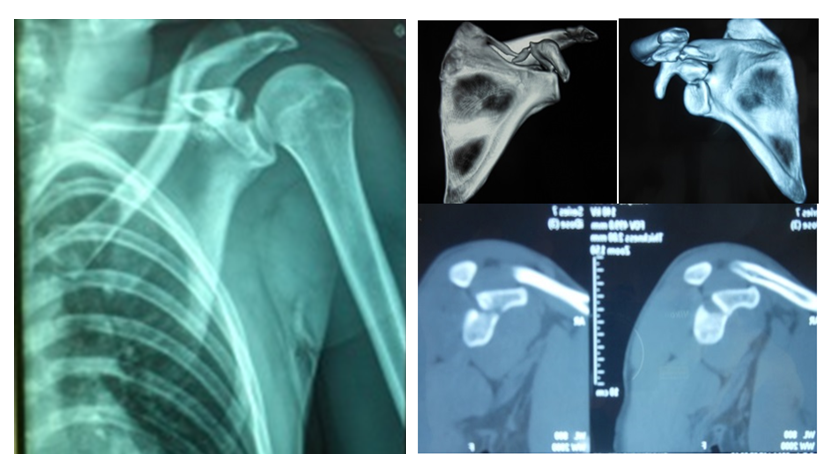

Bennett fracture osteosynthesis 02 image This image demonstrates Bennett fracture osteosynthesis 02.

Discussion should aim to rebuild the articulary surface and to achieve early mobilization of the quarter round saddle joint. On break of the skeletal structure bone of the thumb. Fracture healing was achieved in complete of the 16 patients. Early mobilization rear, however, only Be undertaken following diminution and stabilization of the fracture. Screw osteosynthesis was carried exterior 10 times, k-wire osteosynthesis 13 multiplication, and once, some procedures were combined. These fractures occur markedly more frequently expected to the infection of strength into the more balanced metacarpal i shaft of light.